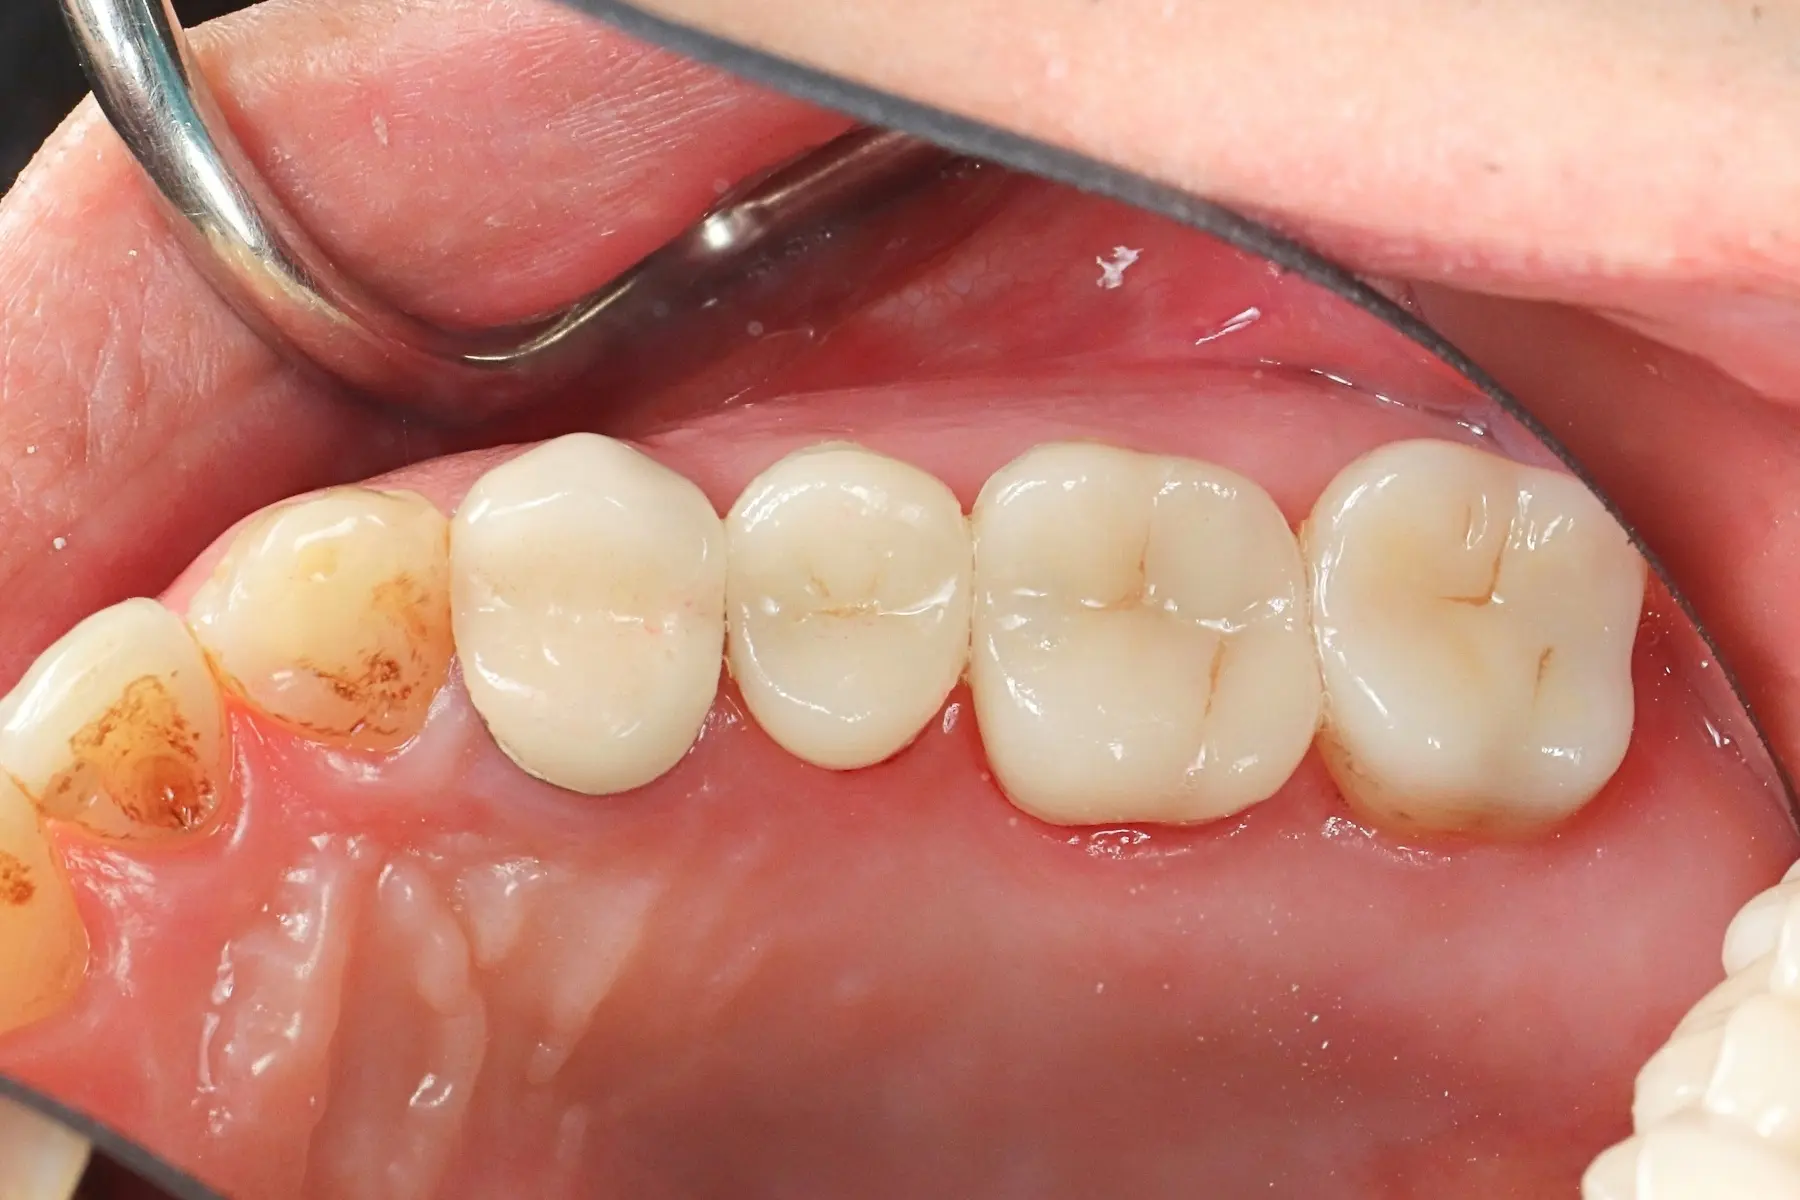

• 術前 43

術後 41

牙橋

主治醫師

• 楊明憲

治療時間

約1年4個月

主訴

吃東西左邊後牙會痛